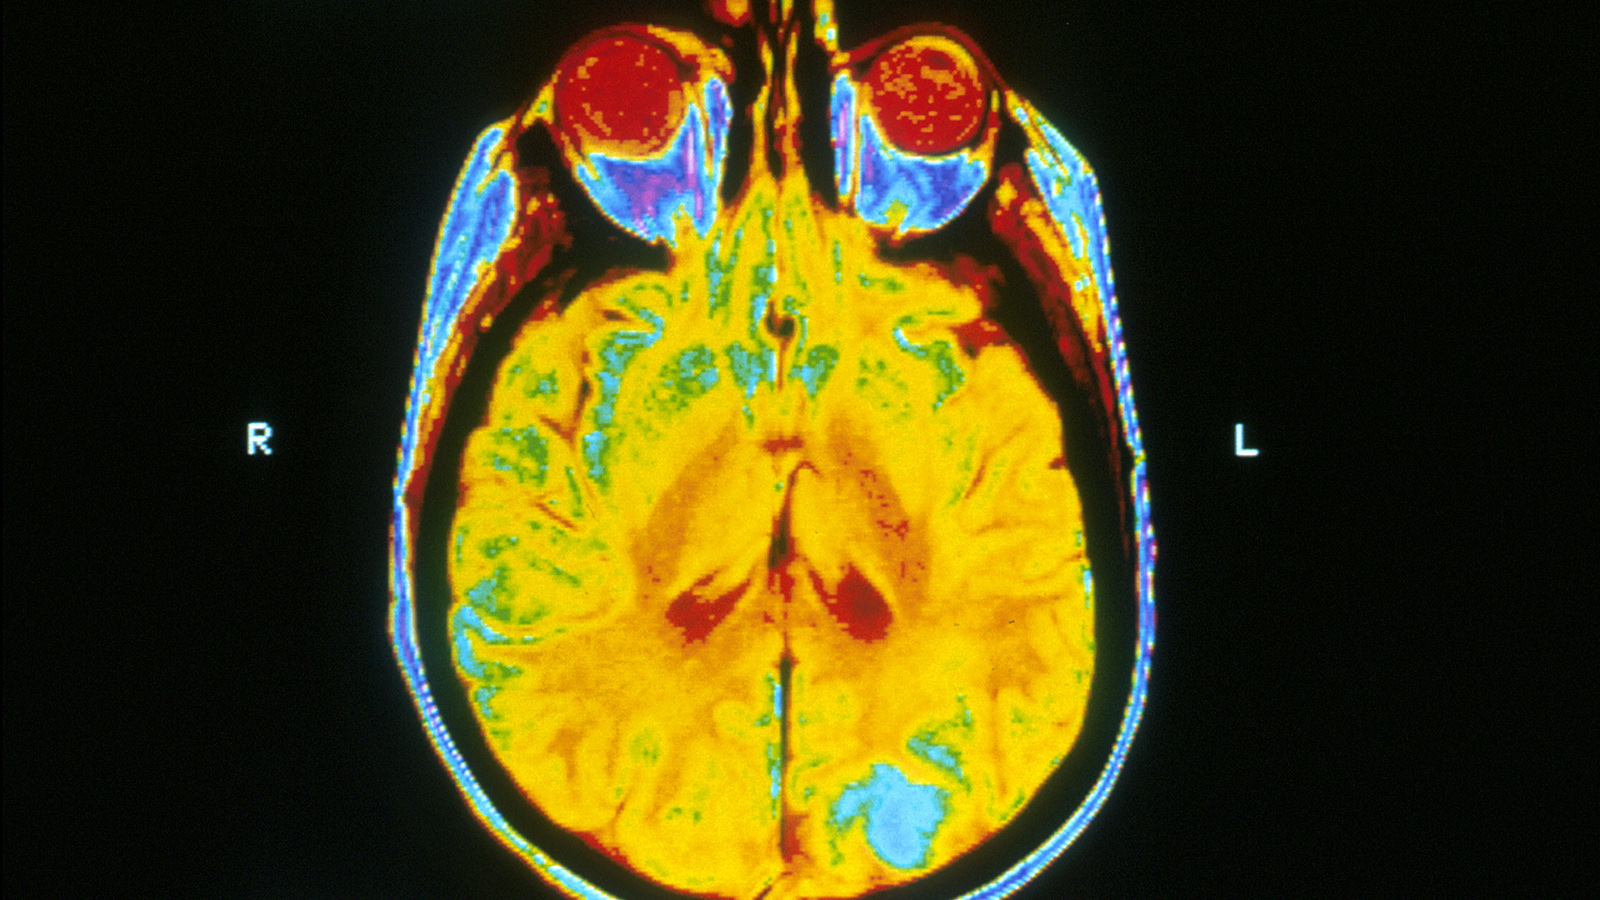

This brain image is 64 million times sharper than standard MRI

A new brain imaging technique that generates ultra-high resolution images of mouse brains could revolutionize neuroscience research.